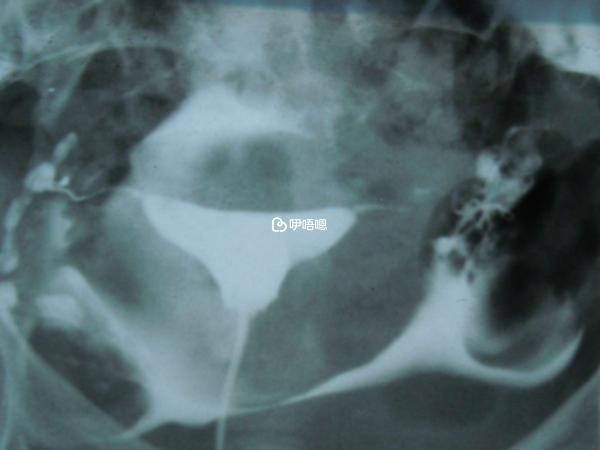

國婦嬰做了一系列常規檢查都正常後,讓我做了造影,顯示說痛而不暢。後來發現身邊大部分都是不通或者痛而不暢。然後醫生又告訴我,其實是通的,只是他們比較嚴格。

網上說,造影以後特別容易懷孕,所以造影后我又等了三個月。還是不孕。因為內膜有一個息肉,加上通而不暢的事情,18年2月的時候我又去做了宮腔鏡。

做完宮腔鏡說我雙側輸卵管暢通,我想應該馬上就能懷孕了吧,又等了三個月,還是沒動靜。三個月後,我接受了醫生的建議,開始做人授,一次、兩次,他們說三次人授不成功就沒希望了,人授兩次後,我很焦慮,又想回去看中醫。